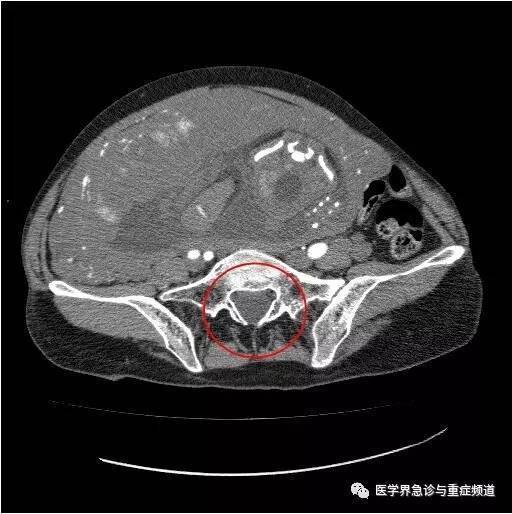

【病例】输卵管妊娠破裂1例ct

图片尺寸720x740